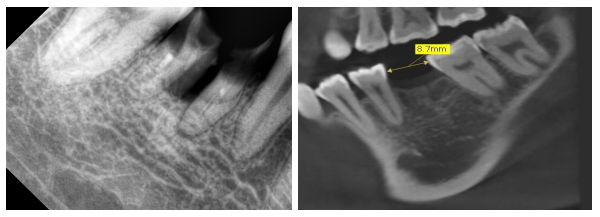

术前X线片

2016-2017术前X线

治疗过程:46必兰局麻下,切开翻瓣,预备种植钉道,植入ITI4.8*10mm种植体一枚,颊侧植入Bio-oss骨粉,覆盖骨膜,严密缝合。